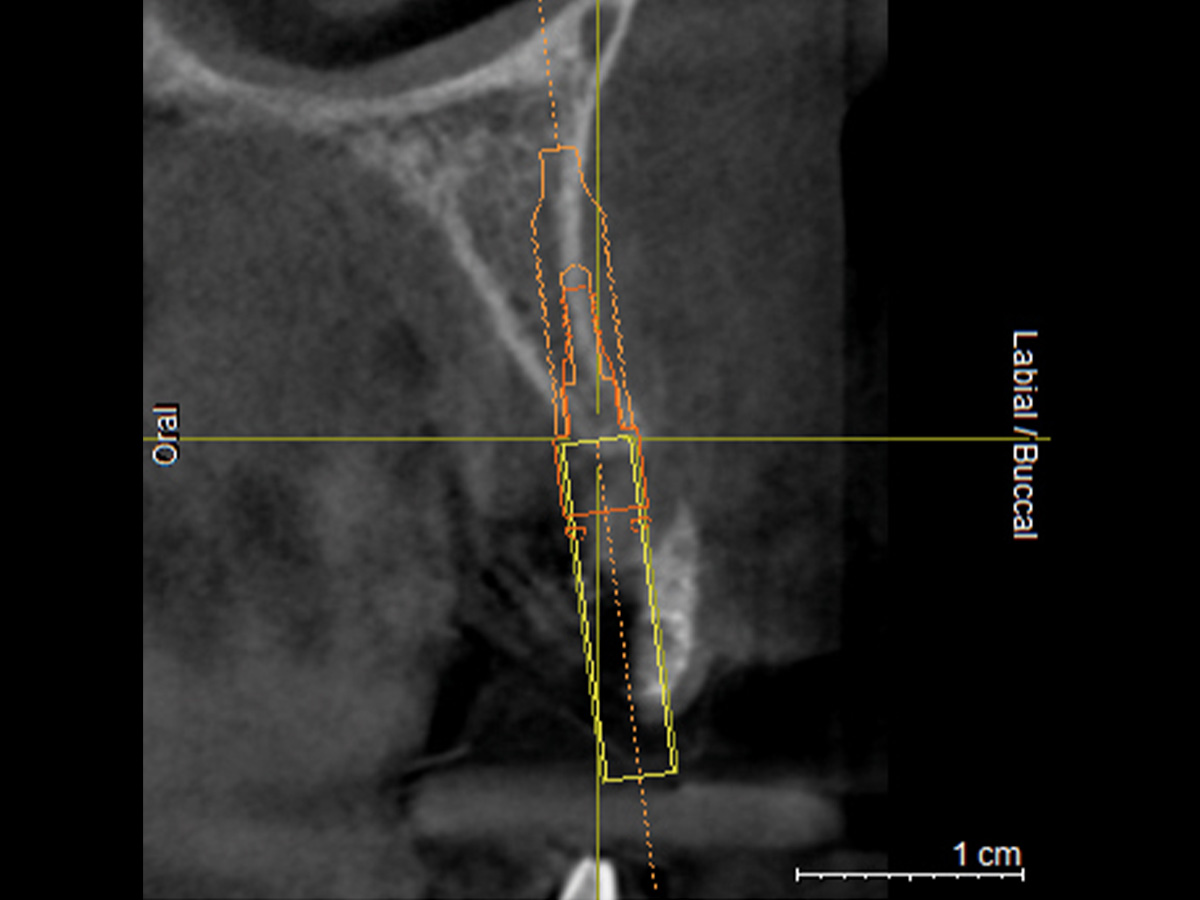

Abbildung 2

DVT mit Implantatplanung zeigt die atrophe Knochensituation mit geplantem Implantat.